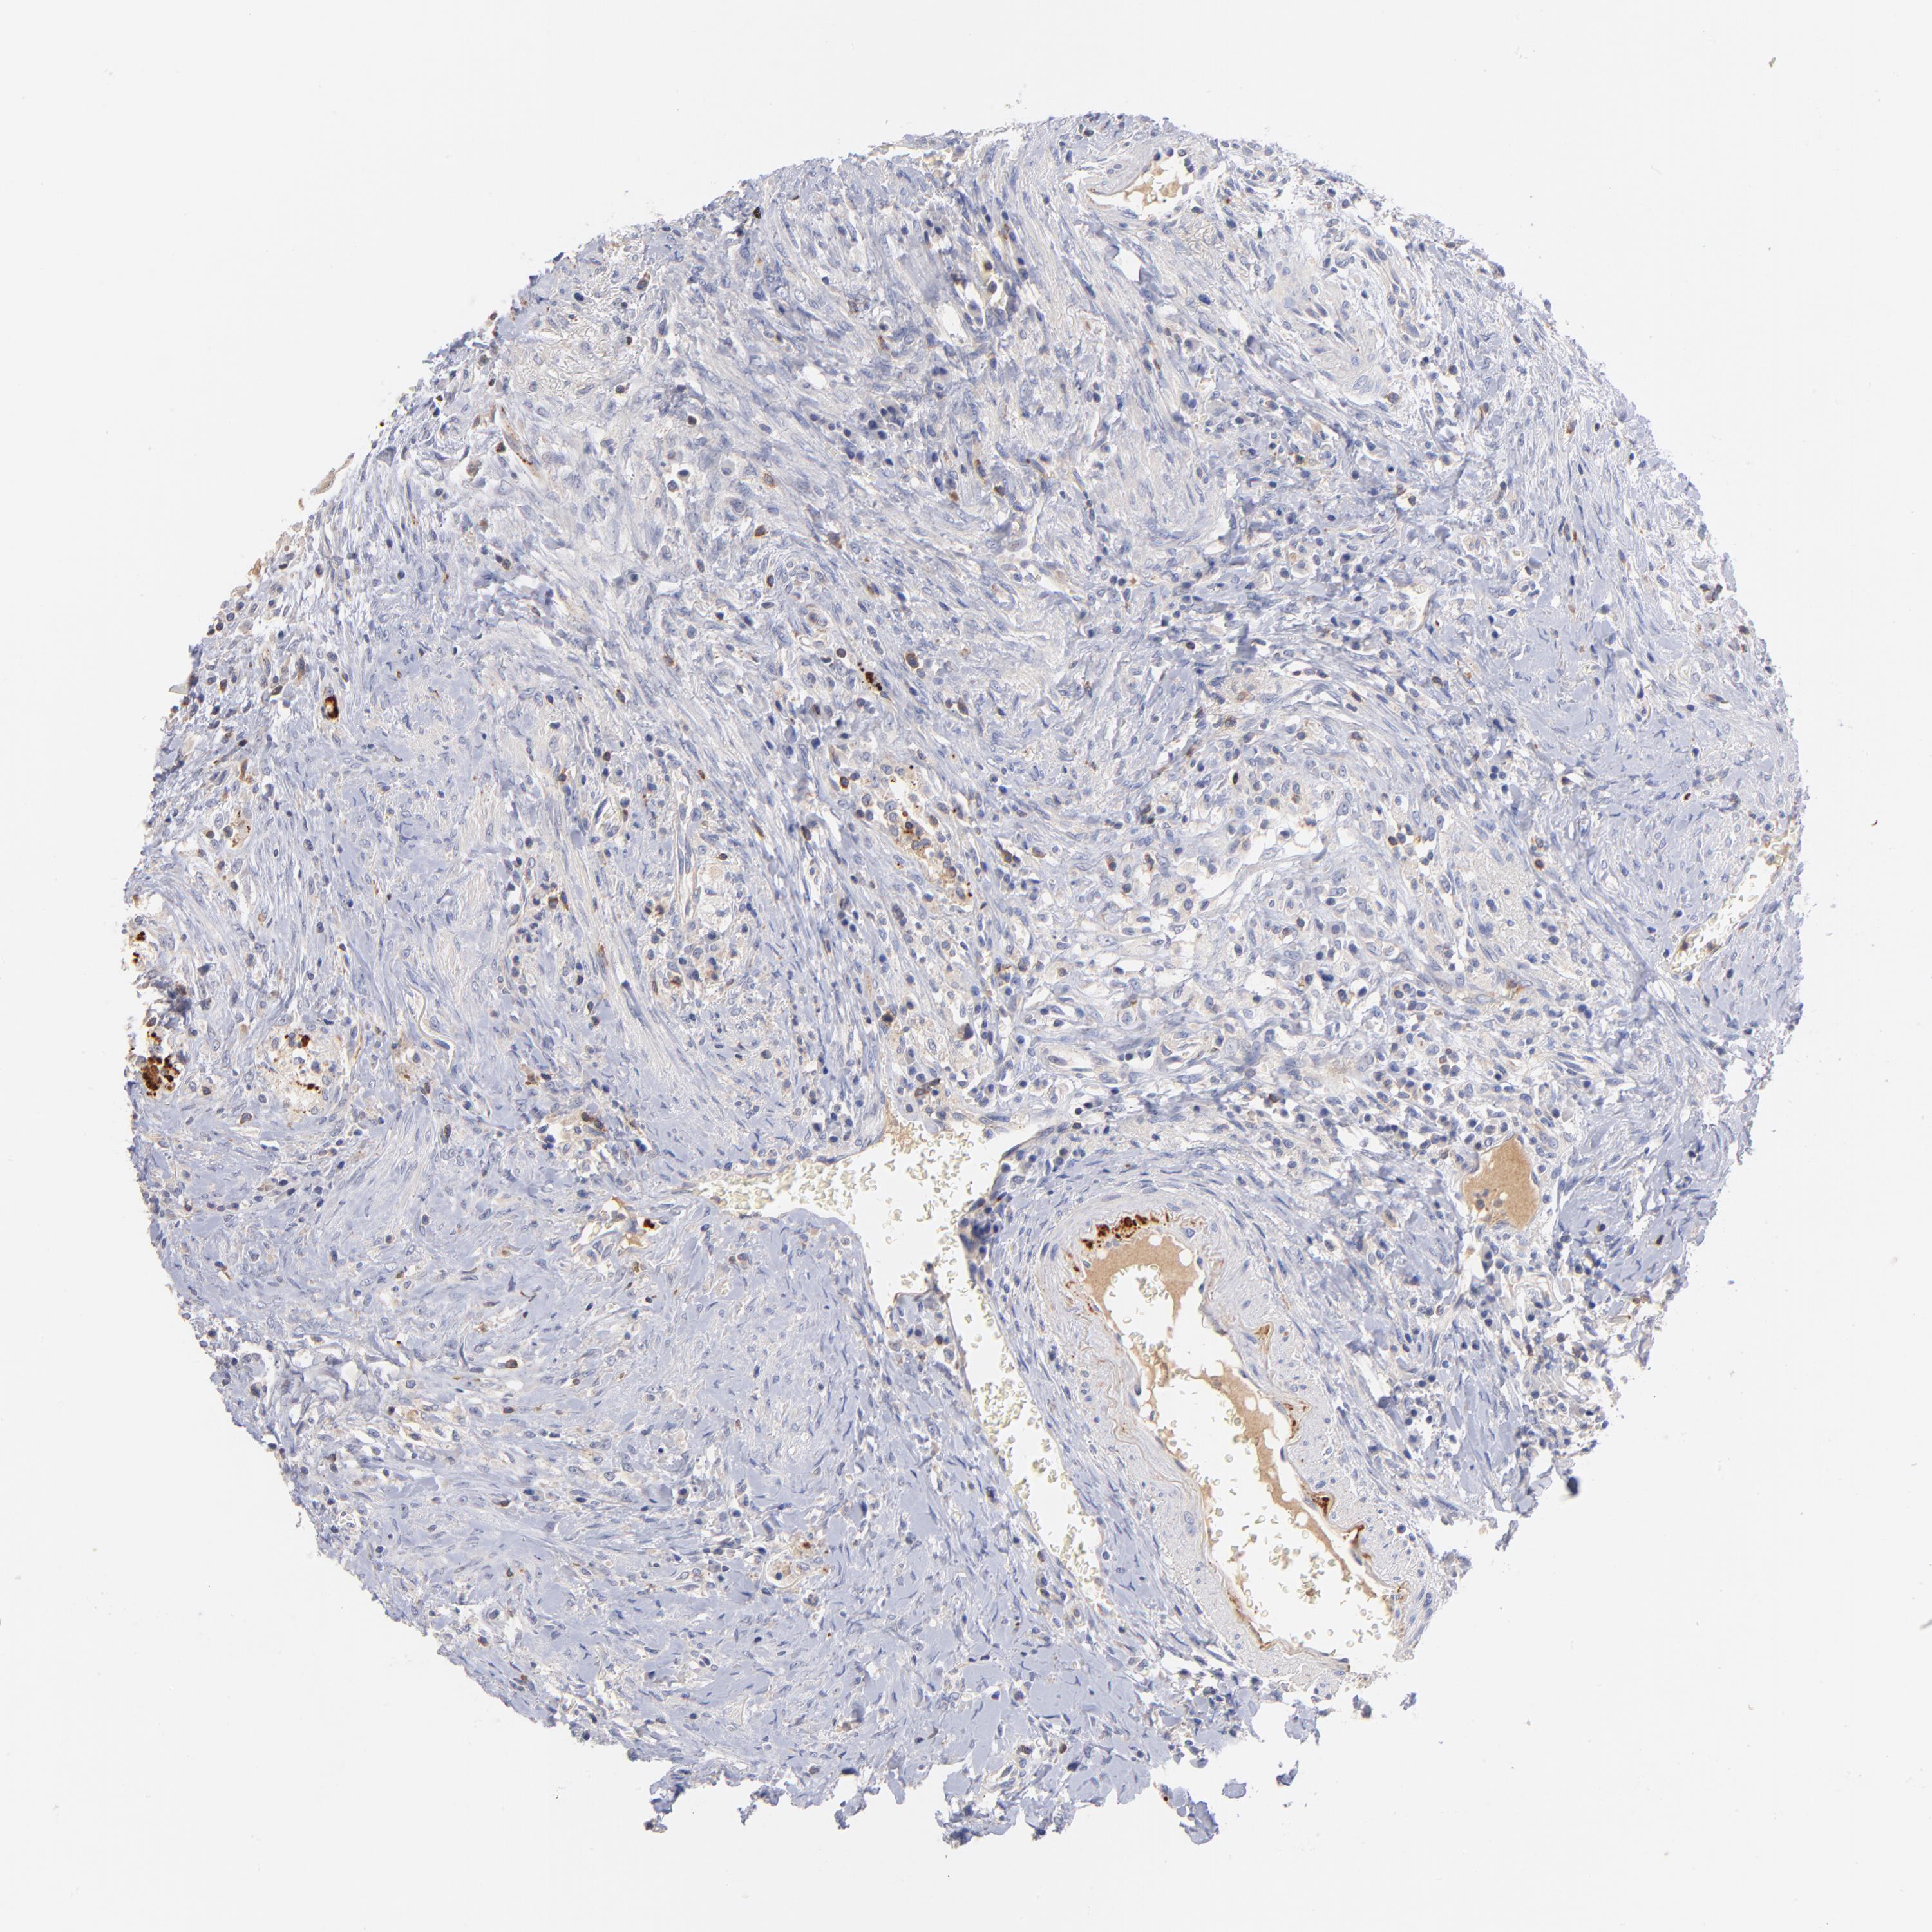

CANCER COLORECTAL CANCER Show tissue menu

Colorectal cancer

Colon adenocarcinoma

KREMEN2 is not prognostic in Colon Adenocarcinoma (TCGA)